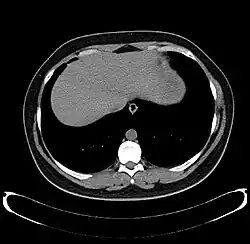

-

Axial CT image showing anomalous hepatic veins coursing on the liver's subcapsular anterior surface[74]